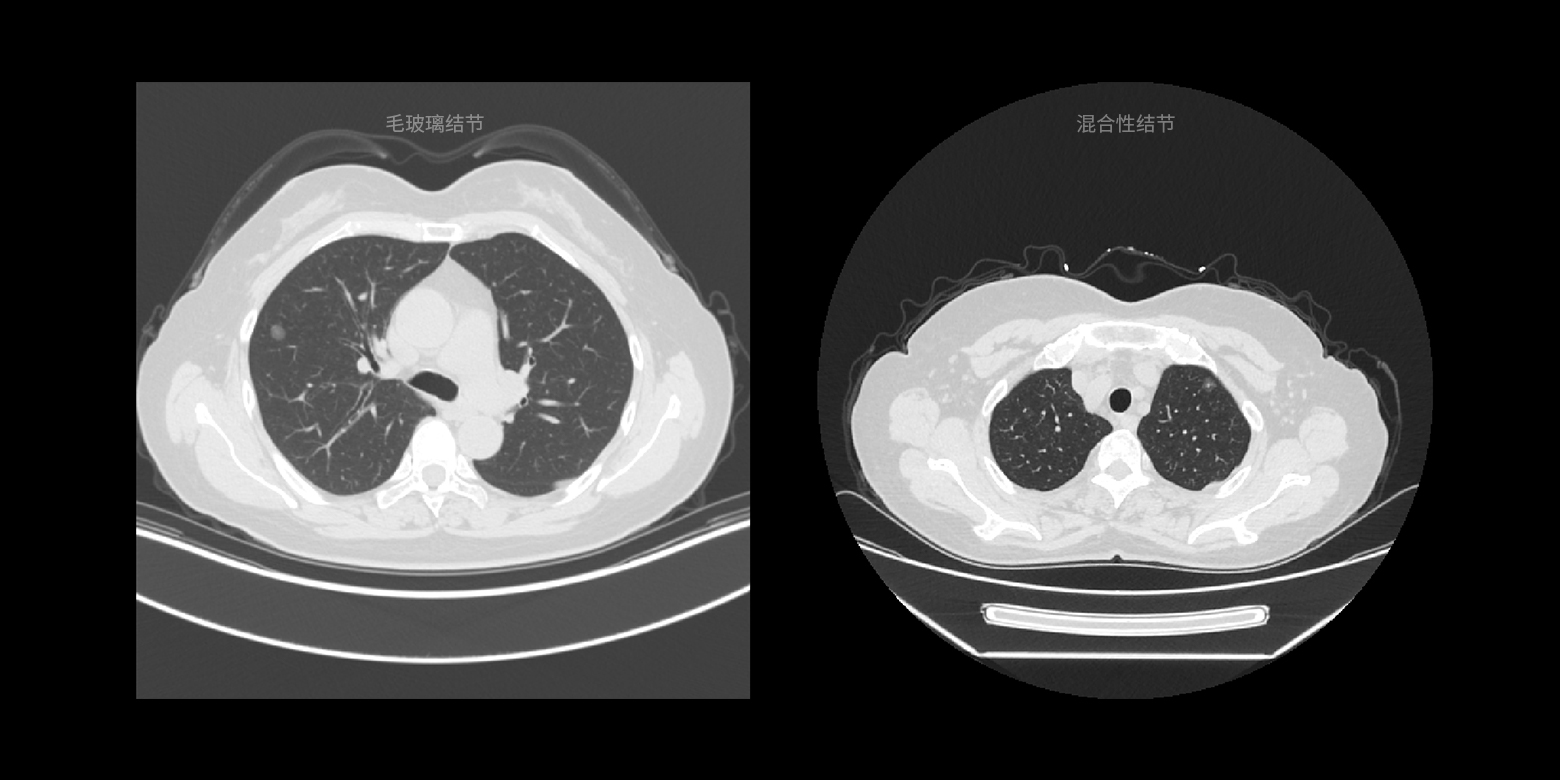

病灶類型鑑別

根據國際通用的診斷指南以及頂級醫生的診斷經驗,針對臨床診斷的病變類型進行快速鑑別,降低相似病變的誤診概率。